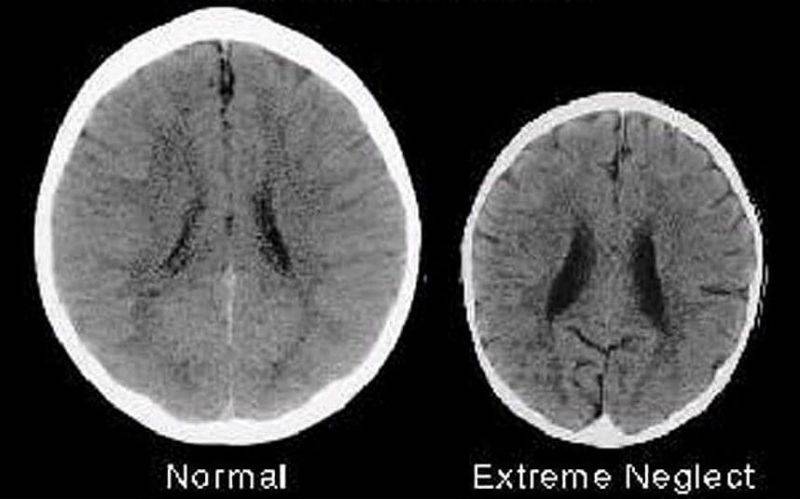

Vi mostriamo una foto (qui sopra) di due cervelli di dimensioni diverse. Si tratta dei cervelli di due bambini di tre anni ed è evidente che il cervello a sinistra è molto più grande di quello a destra e presenta meno aree scure e sfocate.

Come appare in didascalia, il cervello a sinistra è “normale“, mentre quello più piccolo a destra presenta delle anomalie ed è indicato come “abuso estremo“.

Nell’immagine che vi mostriamo sopra il cervello di sinistra è molto più grande di quello a destra più piccolo, che presenta macchie scure e aree sfocate, quasi assenti nel primo.

I cervelli appartengono a due bambini di tre anni e le differenze sono consistenti.

Al cervello sulla destra mancano delle aree fondamentali, presenti invece in quello a sinistra. Si tratta di mancanze che incidono sulle capacità del bambino con il cervello più piccolo:

- questo bambino sarà meno intelligente da adulto rispetto a quello con il cervello più grande,

- sarà meno in grado di entrare in empatia con gli altri

- e avrà maggiori probabilità di diventare tossicodipendente ed essere coinvolto in crimini violenti.

Inoltre il bambino con il cervello più piccolo avrà maggiori probabilità di restare disoccupato e dipendente dai servizi sociali, e potrà sviluppare problemi mentali o altri gravi problemi di salute.

Queste dimensioni diverse del cervello nei due bambini di tre anni non dipendono tuttavia da una malattia, ma da come sono stati trattati da piccoli. Una scoperta sconcertante.

La grande differenza nelle dimensioni e nello sviluppo di questi due cervelli, infatti, non dipende da una malattia o da un incidente, ma dal modo in cui i due bambini sono stati trattati dalla madre.

Il bambino con il cervello più grande e sviluppato è stato amato dalla madre, che è stata sempre presente e sensibile alle sue esigenze.

Il bambino con il cervello più piccolo, invece, è stato trascurato e abusato.

Proprio la differenza di trattamento spiega perché il cervello di un bambino si sviluppa in modo completo e l’altro no.